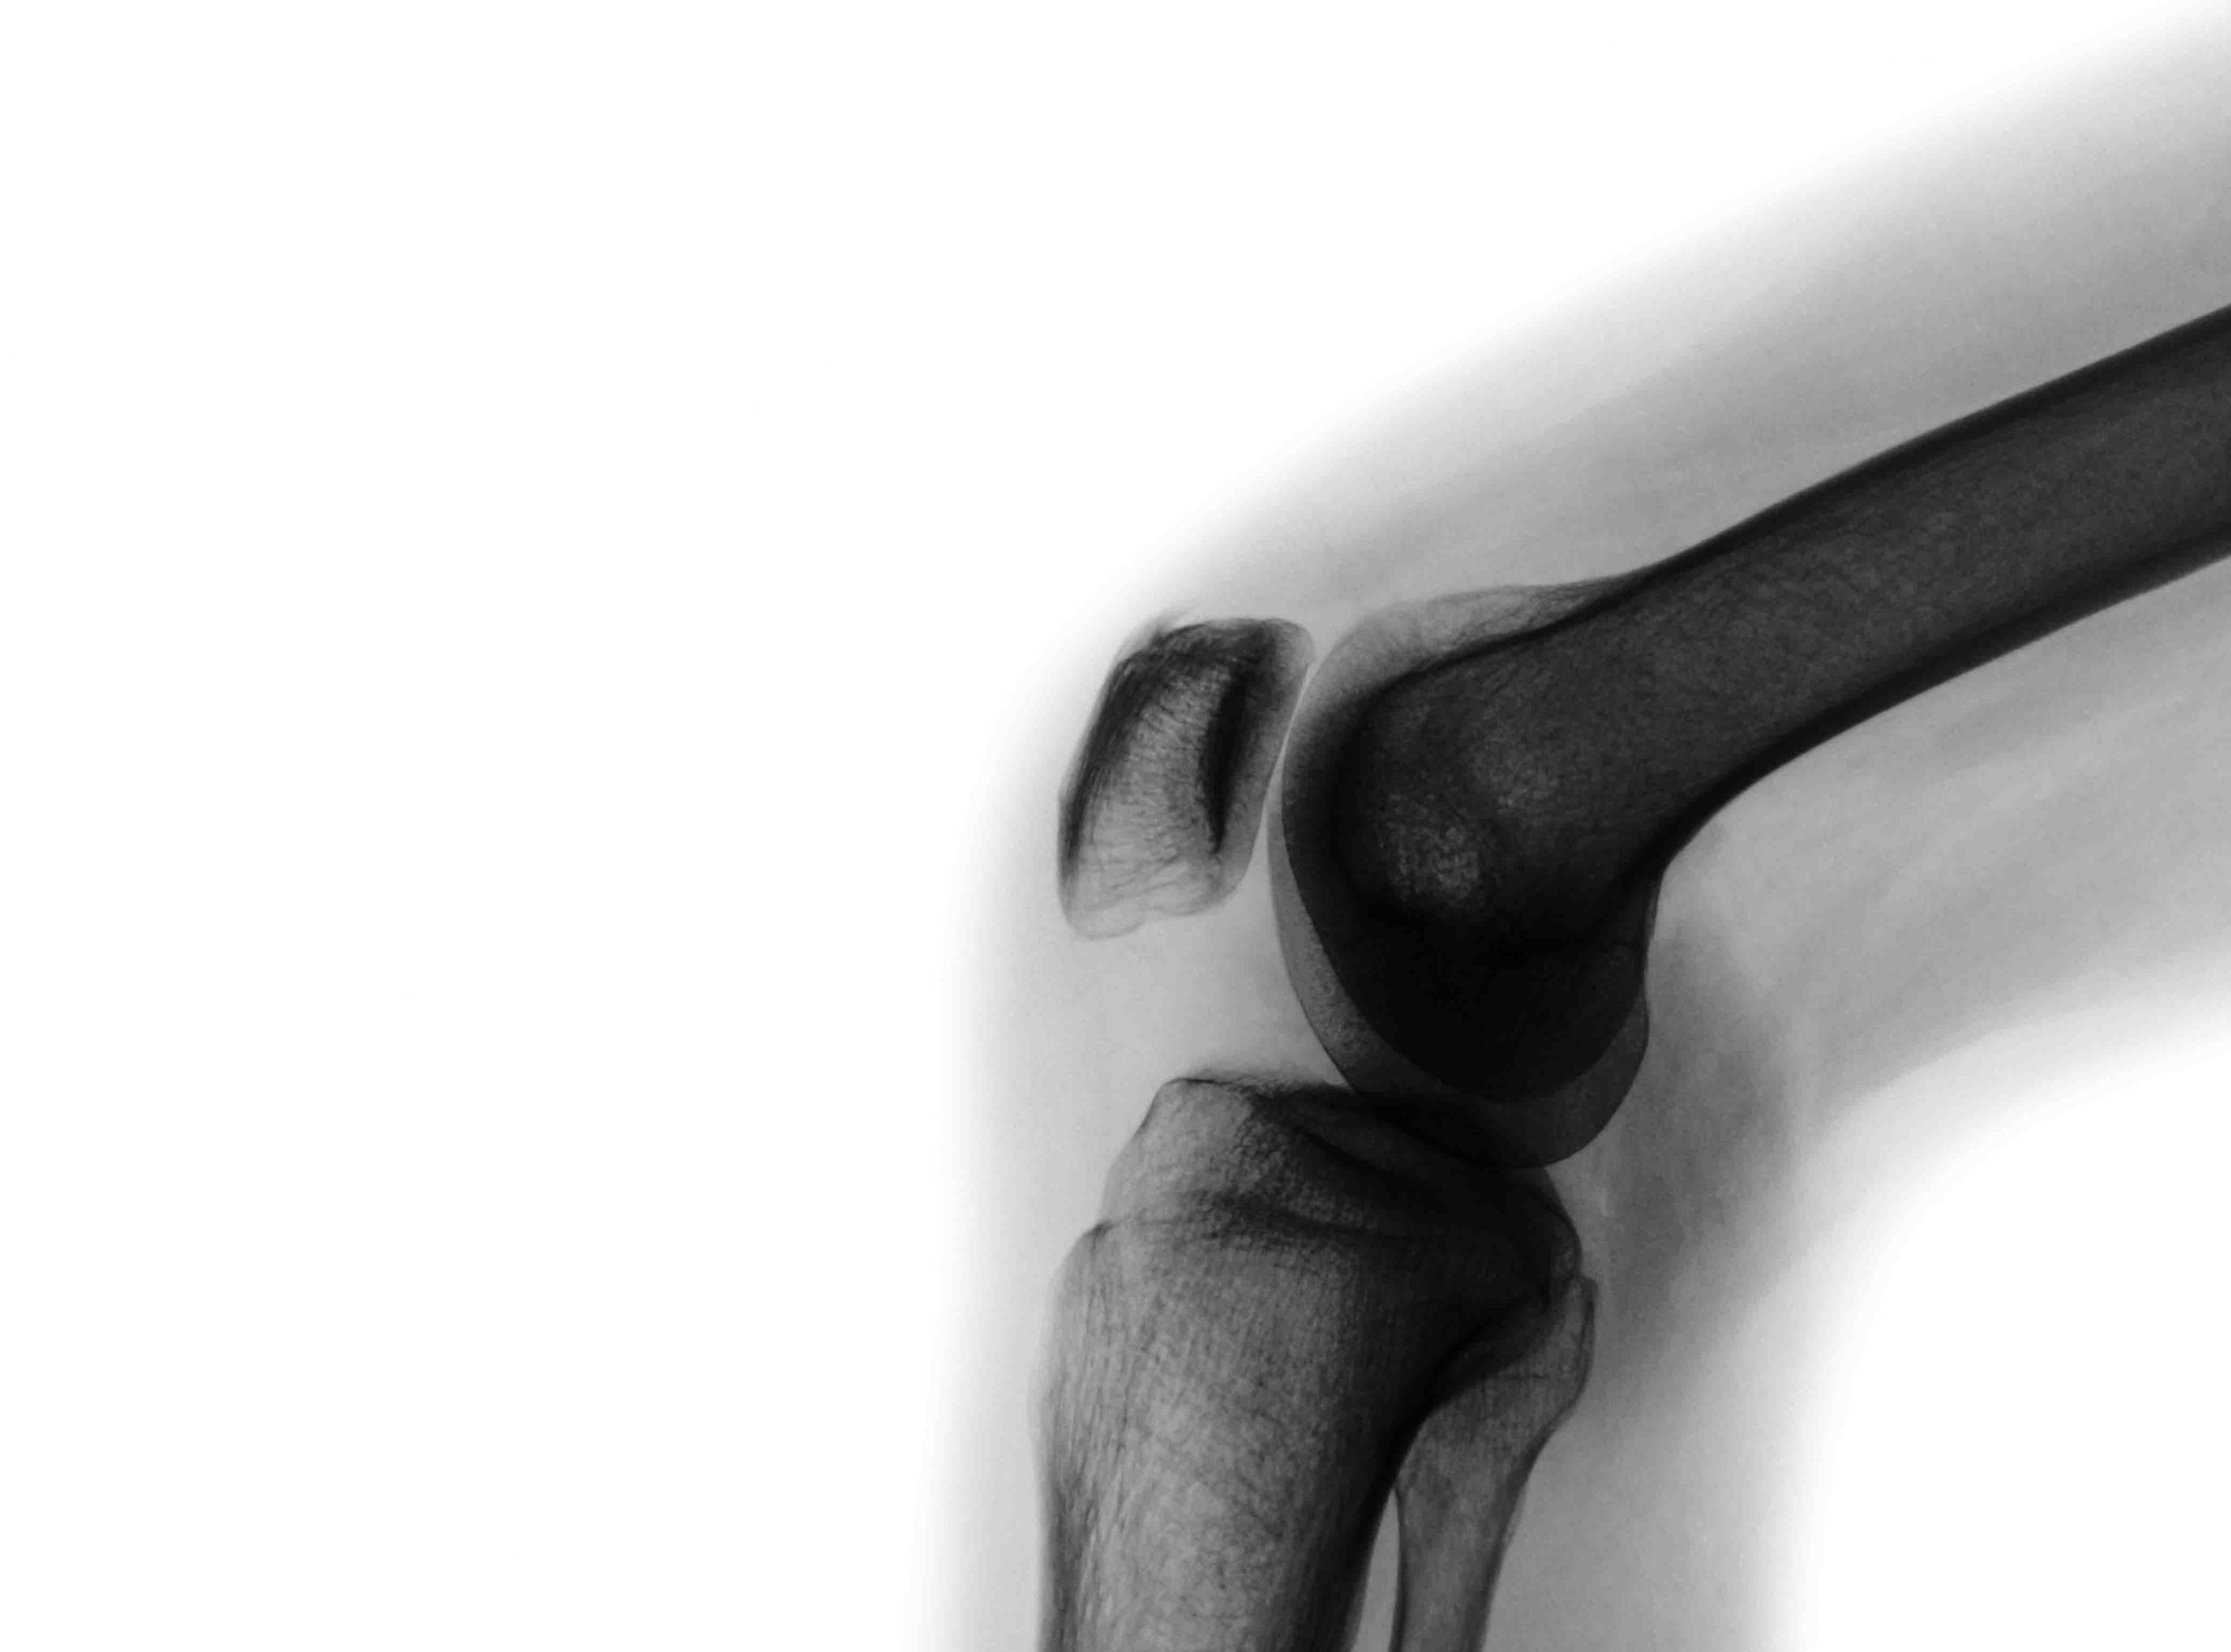

Osteoarthritis is the most common lifestyle disease in those aged 65 years and older, but it can also affect those as young as 30. Around 2.2 million Australians suffer from Osteoarthritis –a condition that affects the whole joint including bone, cartilage, ligaments, and muscles.

Osteoarthritis can cause pain and stiffness of the joints and can affect your ability to do normal daily activities such as walking and climbing stairs.